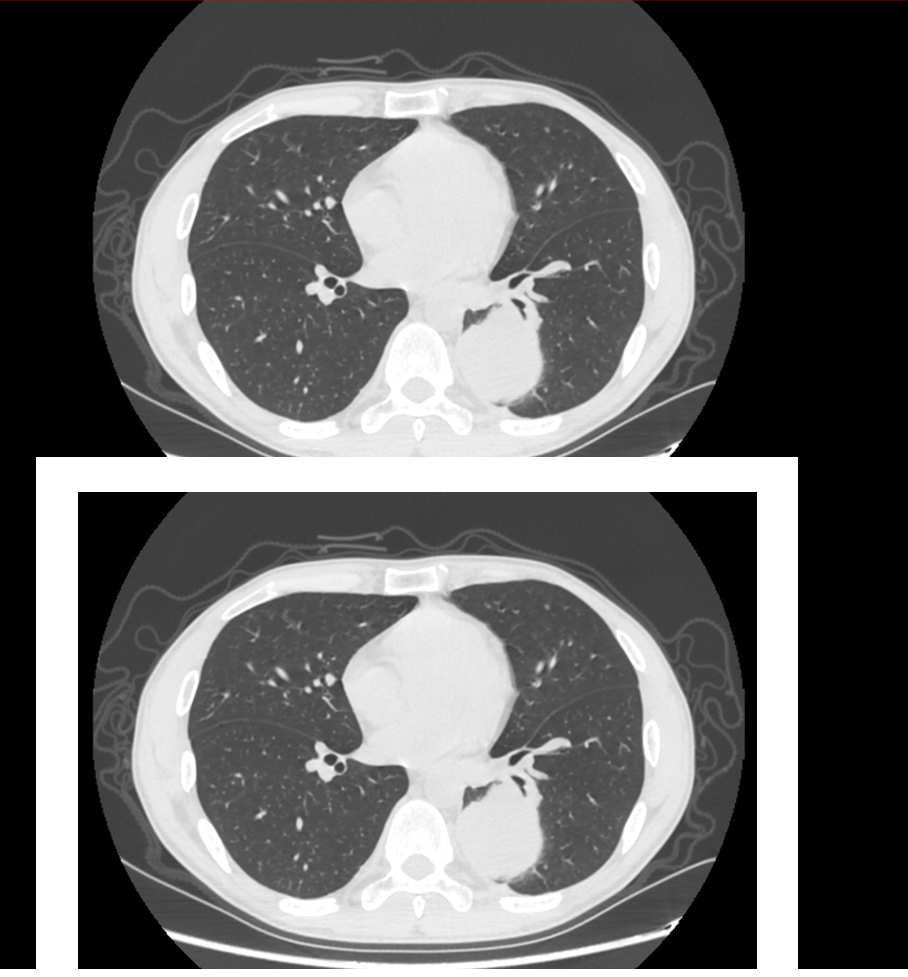

做出來的胸部CT be like:

白色的框子就是我們的混檢支架,這樣並不影響影像科醫師閲片。我們可以進行命名,上面的叫上患者(Up Patient,UP),下面的叫下患者(Down Patient,DP)。

“這個UP氣胸了。”聽起來非常專業。